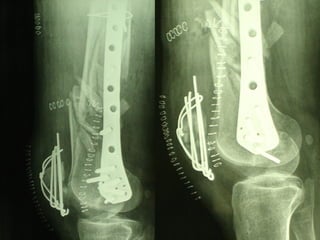

Dal Gennaio 2000 al Dicembre 2005 27 placche LISS di femore

INDICAZIONI COMUNI Fratture sovracondiloidee Fratture intercondiliodee Fratture diafisarie distali PARTICOLARI Fratture con grave osteoporosi Fratture periprotesiche

VANTAGGI CHIRURGIA MININVASIVA Mini Open Inserimento della placca sottocutaneo per scivolamento Viti percutanee Preservazione dei tessuti molli Ridotto danno vascolare Rapida ripresa funzionale

F, 68 y

LISS  NCB

NCB

Conclusioni Riduzione  anatomica Minimo trauma chirurgico Corretto equilibrio fra elasticità e stabilità Precoce mobilizzazione